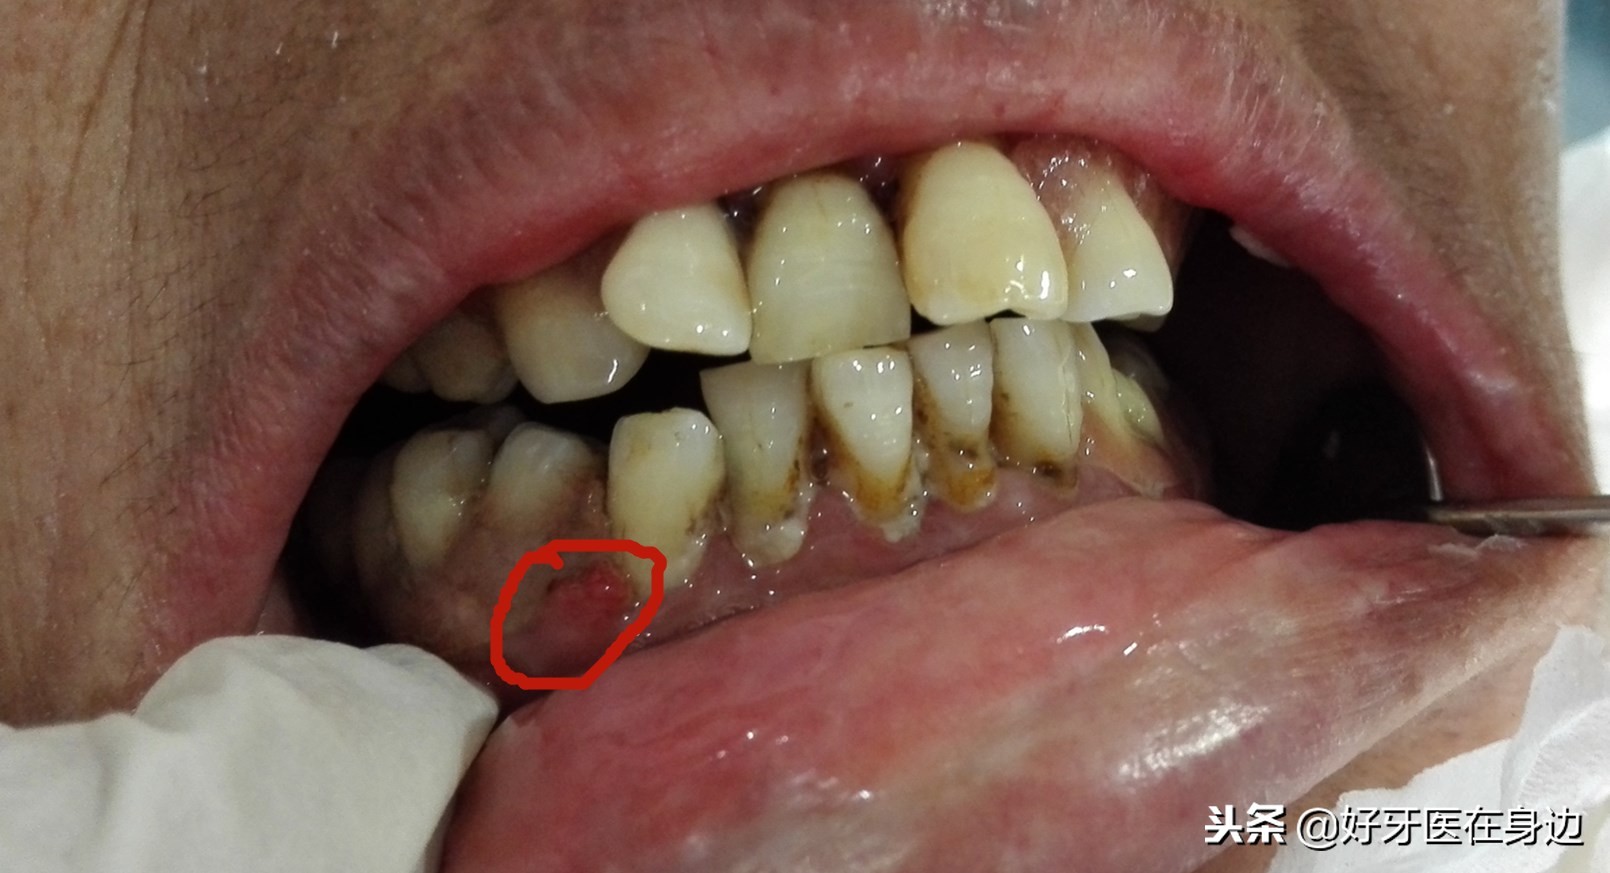

不良修复体导致的牙龈红肿

1.牙龈红肿、口臭:由于牙龈被塑料包住,口腔卫生无法清理,食物残渣残留,以及塑料对牙龈的刺激,都会造成牙龈发炎、肿胀,细菌发酵而产生臭味!

5.癌变:长期的塑料刺激以及边缘毛糙都会导致口腔粘膜的癌变!